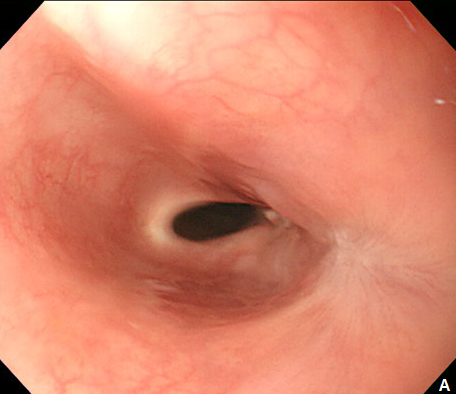

Figure 1 Esophageal subepithelial tumor (SET).

(A) An esophagogstroduodenoscopy (EGD) showed a large (4.0 cm) SET at upper to mid esophagus. (B) An endoscopic ultrasonography showed a large hypoeshoic mass originated from muscularis propria layer.